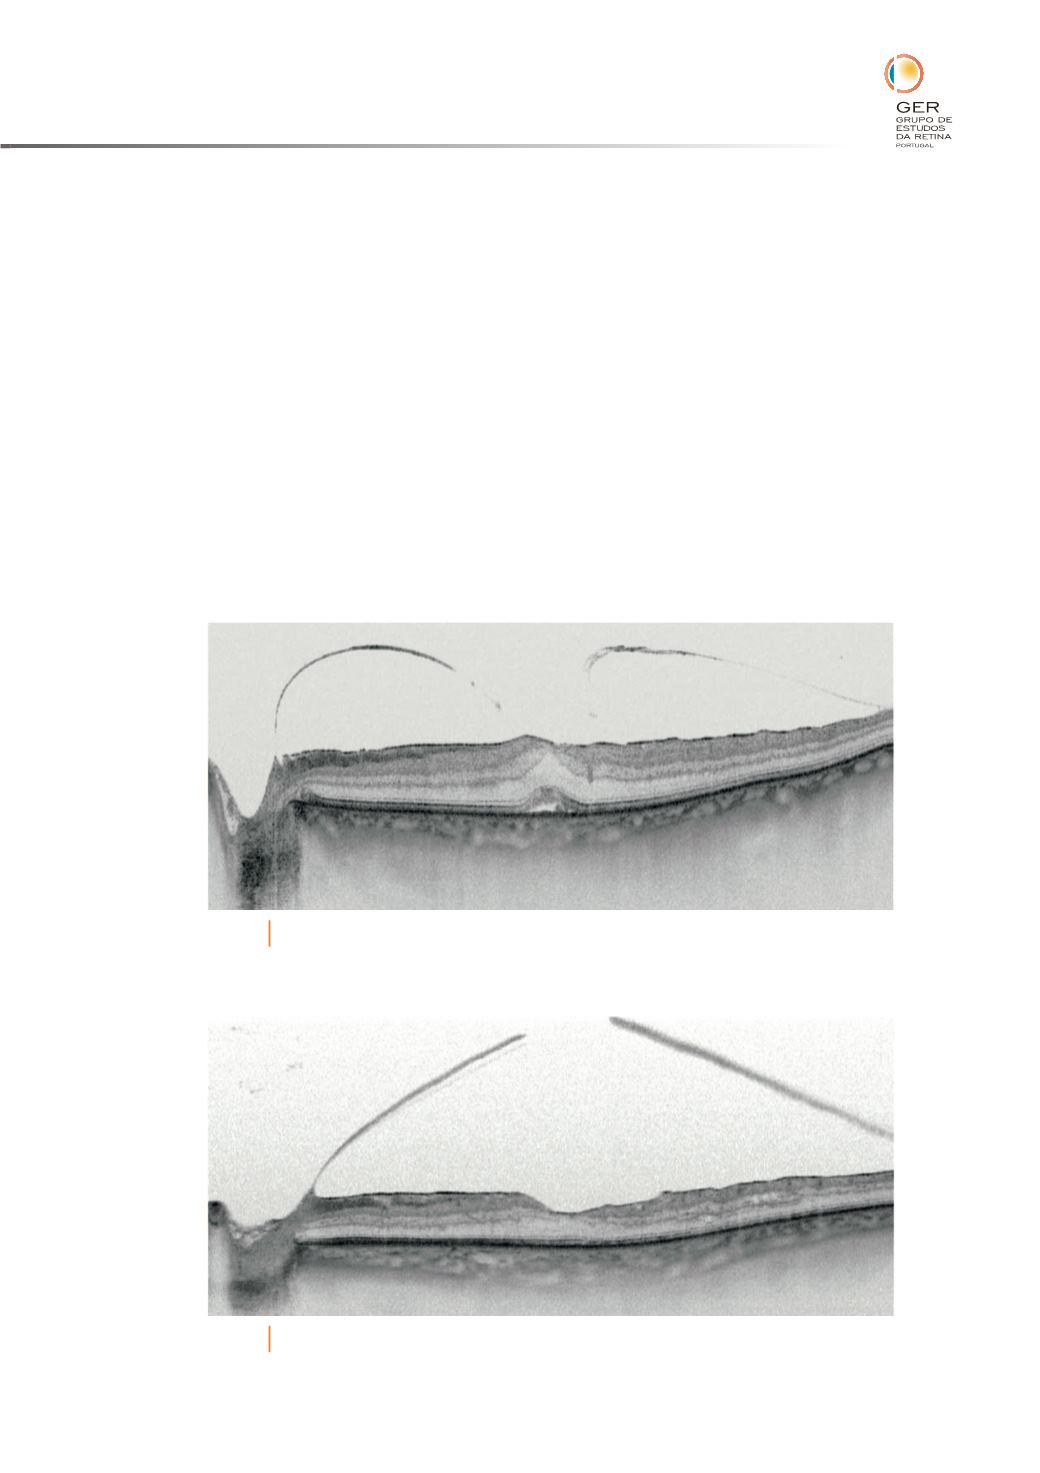

No EMD a relação existente entre o vítreo e a superfície interna da retina é

caracterizada por uma maior aderência, com áreas mais extensas de contacto.

Esta relação vítreo-retina manifesta-se de duas formas: - por um efeito mecânico

apenas; - por forças com efeito na competência dos capilares e consequente

extravasão de `uidos. O aumento da reactividade das células da glia poderá

estar na origem da proliferação epiretiniana. As forças de tracção exercidas

poderão também ter um papel regulador na tensão de oxigénio intraocular

(hipóxia).

A vitrectomia via pars plana estará indicada em certos casos por forma a

aliviar estas forças, melhorando a oxigenação e aliviando o factor mecânico

(Figuras 4 e 5).

Fig. 4

EMD com tração vítreomacular, membrana epiretiniana.

Fig. 5